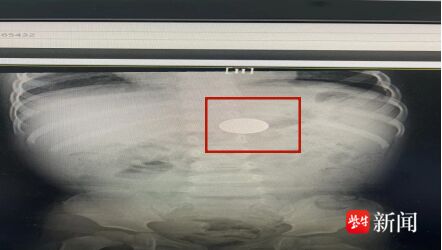

前段时间,这名患儿因为肺炎而被连云港市妇幼保健院儿科收入院治疗,医生在给孩子拍胸片时,意外发现附件中上部消化道异物,综合评估,考虑是硬币的可能性大。

之后,家长带孩子复查,影像报告显示消化道异物仍在原位未排出。

1月6日,家长再次带孩子来院就诊,影像报告明确异物仍存在胃内,医生再次与家长积极沟通,建议立刻通过胃镜异物取出术,保障儿童安全。